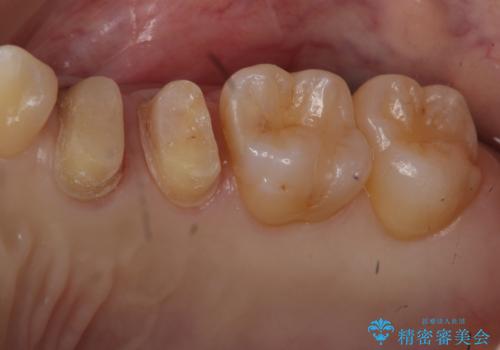

他院の根の治療で一向に治らない、さらに歯根を切ってもらったが良くならない

- 他院で保険治療で根の治療に1年以上通っているが一向によくならないとのことでした。

根の詰め物をした後も歯ぐきからウミが出てくる上に、咬むと痛いとのことでした。

さらに、同じ病院で根の先を切る手術も行なったが症状が改善しなかったそうです。

前回の治療がうまくいかなかった原因として、根の中がまだ汚い状態で、根の先だけを切ってもうまくいかない可能性があったことを説明し、根管治療をやり直すことになりました。